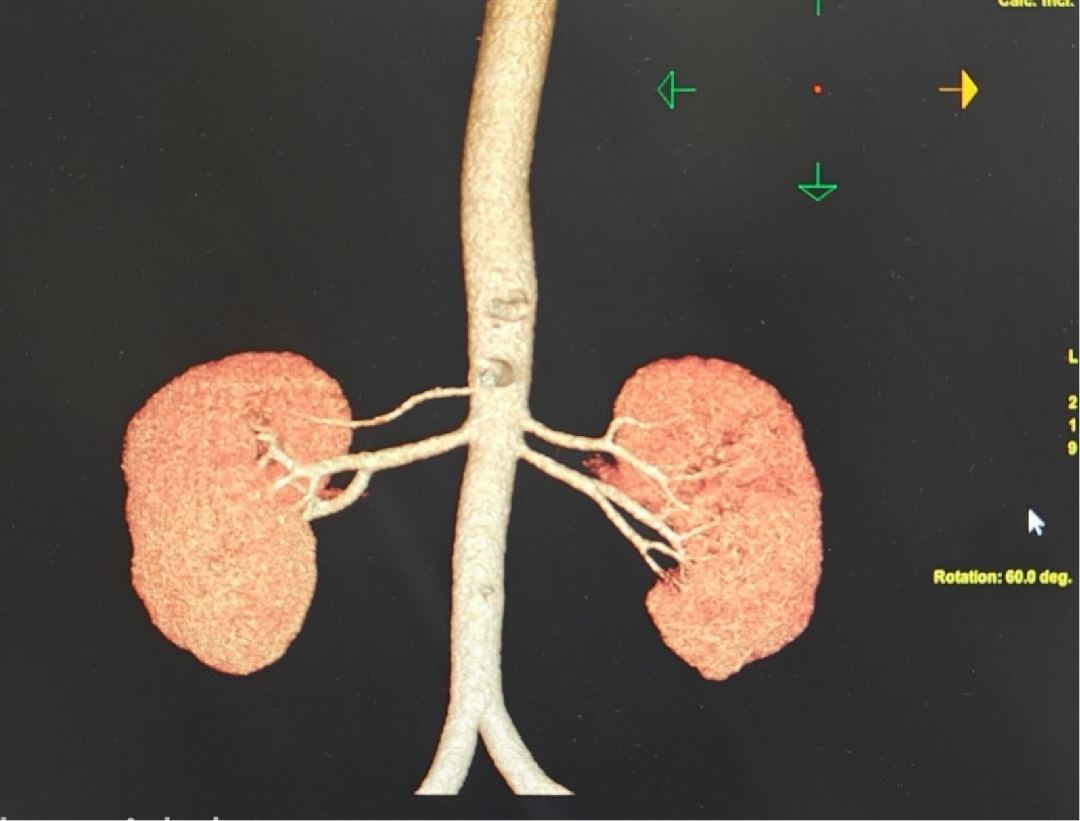

1.高血压成因:肾血管性高血压筛查

诊断结果

双侧副肾动脉;

双右侧肾上腺大小形态如常,其内外侧支无增厚及结节影,肾上腺周围脂肪界面清楚;

双肾盏见斑点状高密度影;

排除肾血管性高血压